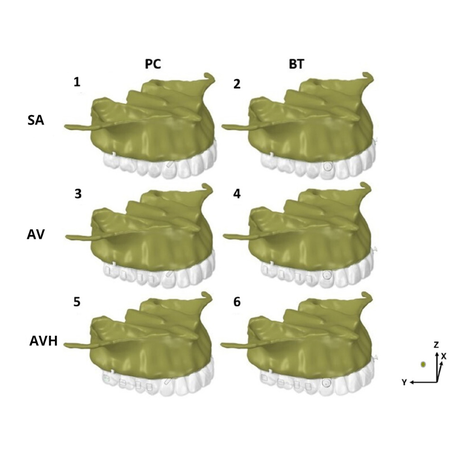

Objetivo: Este estudo investigou a influência de attachments nos dentes posteriores superiores usando alinhadores e ancoragem esquelética extra alveolar, combinada com precision cuts (PC) ou botões (BT) nos caninos superiores. Métodos: Modelos virtuais 3D foram criados a partir de uma tomografia de um paciente adulto jovem, caucasiano, com dentição permanente intacta desde os segundos molares e apresentando má oclusão de Classe II, divisão 1. Foram utilizados seis modelos de...

Objective: This study investigated the influence of attachments on the maxillary posterior teeth using aligners and extra alveolar skeletal anchorage applied to precision cuts (PC) or buttons (BT) on the upper canines. Methods: 3D virtual models were created from a tomography of a young adult Class II, division 1 Caucasian patient with healthy and non-restored full complement of permanent teeth (except third molars) was used. Six finite element models of the maxillary teeth with aligners and...